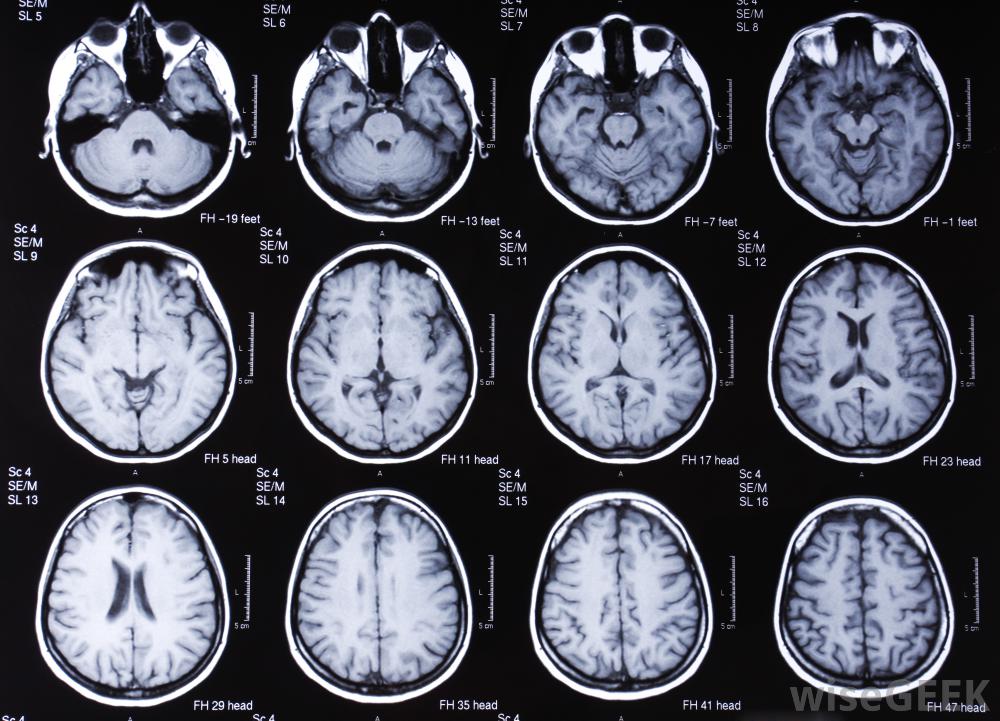

核磁共振成像和PET掃描有什么區別(the Difference between an MRI and PET Scan)?

核磁共振成像和PET掃描的主要區別在于每種方法都能喚起健康提供者所依賴的圖像。這些掃描在確認和探索可能的診斷方面非常有價值,沒有這些診斷,醫生和其他專業人員將無法有效地治療疾病。功能上,這兩種影像學研究都是通過穿透周圍結構來達到相似的目的;然而,他們的方法不同。簡單地說,核磁共振成像使用磁技術,而PET掃描則檢測身體內的物質以產生活躍的圖像對大腦進行的MRI掃描。MRI和PET掃描都是縮寫。MRI是磁共振成像的縮寫,PET是正電子發射斷層攝影術的意思,雖然這兩個詞對外行人來說都有點嚇人,核磁共振成像儀使用磁場和無線電波來生成內臟和骨骼的圖像結構。磁共振成像使用多個磁場,每一個磁場都非常強,以物理方式排列身體內部結構中的特定原子這些磁場使原子中心的原子核旋轉運動,這些變化是由于位置的差異以及原子的類型造成的。這些轉速的差異被記錄下來并轉換成磁共振圖像。這個圖像通常反映了身體的內部結構磁共振成像的優勢在于它們能夠顯示軟組織的離散差異,特別是大腦、心臟、肌肉和生長核磁共振成像和PET掃描在形態上有很大的不同。雖然核磁共振成像使用磁場,但一種活性成分是PET掃描成功的關鍵。這種物質通常被注射到身體的某個特定區域或被攝取,隨著這種放射性示蹤劑的衰變,它發射帶正電的粒子,這些粒子是用專門的設備收集起來的。發射的差異顯示了人體系統的工作原理。功能差異可以用計算機圖像上不同的亮度和顏色來表示醫學專業人員可以復查MRI掃描,以確定是否有內傷或疾病的跡象。重要的是要認識到MRI和PET掃描在方式上有根本的不同獲取他們的圖像以及他們可能被利用的環境拍攝和解釋這些圖像需要大量的知識,這就是為什么只有受過訓練的專業人員才應該管理這些測試或從中得出結論。這些測試是極其復雜的程序,只有受過訓練的人才能完全理解其機械過程MRI掃描通常用于診斷損傷或發現異常。